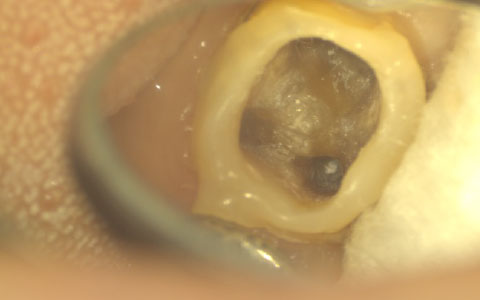

最先端の精密治療

マイクロスコープや三次元レントゲンCTを使用し、精度の高い診査、診断、治療を行なっています。高倍率での治療はとても繊細で精密な技術が要求されます。当院は常に研鑽し、患者さんと向き合い、確かな技術で治療しています。